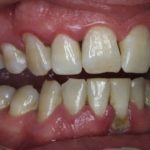

Хронический периодонтит зуба боли практически не вызывает, если речь идет о фиброзной форме. Только по рентгену можно диагностировать недуг. Ощущается тяжесть, подвижность пораженных зубов, их оттенок может меняться. Бывает так, что человек живет много лет с хронической формой и не подозревает об этом, поскольку визуального осмотра порой недостаточно для постановки диагноза. При обострении симптомы такие же, как при острой стадии

Гранулематозный периодонтит приводит к образованию гранулемы, но этот процесс не отмечается явными симптомами. Хотя люди могут отмечать подвижность зубов, изменение их оттенка или боли при приеме пищи. Также может выпасть ранее установленная пломба. Если киста при росте смещается в сторону, при пальпации чувствуется набухание десны, небольшое уплотнение в пораженной области.